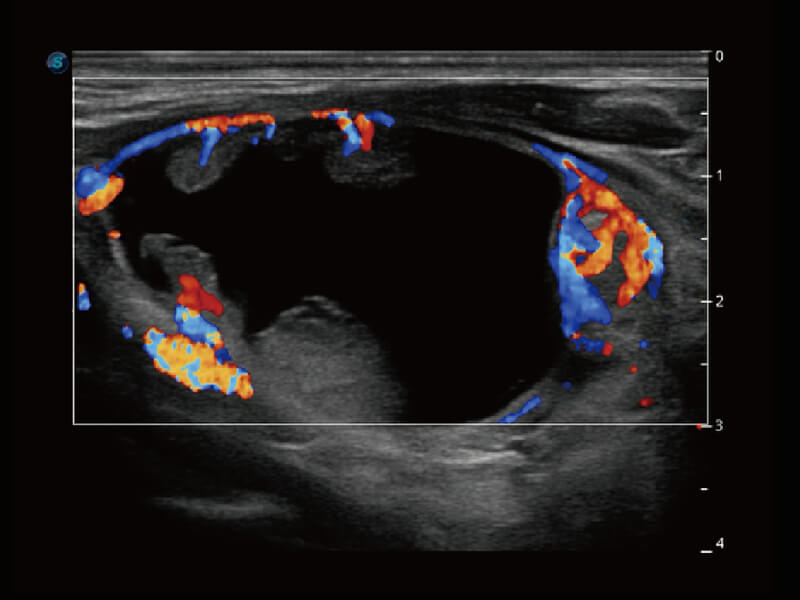

成像功能

性能优异的硬件架构,极大提升超声系统的运行效率和数据处理能力。相比以往超声成像系统,Wis+平台为您带来极快的响应速度和成像帧频,提升检查流畅度。